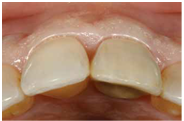

此案例是no.9(即左上正中門牙)有horizontal-oblique fracture的情形 (fig 5,6)

(Fig 5,6)